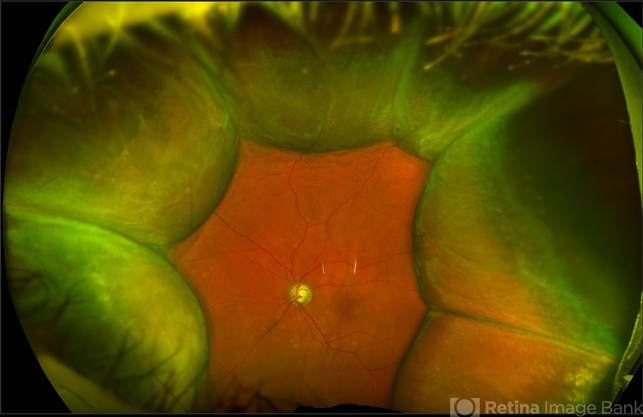

- choroidal detachment, Optos, ultra-wide field imaging, left eye, superior retina, pseudocolor, fundus photograph

- Left ultra-wide field photograph of an 81-year old female with a choroidal detachment affecting her left eye. Patient had a stent placed November, 2021 and following the procedure she complains of variable blurred vision and severe constricted visual fields. She presented at our office with flashes a month prior but without pain or floaters.